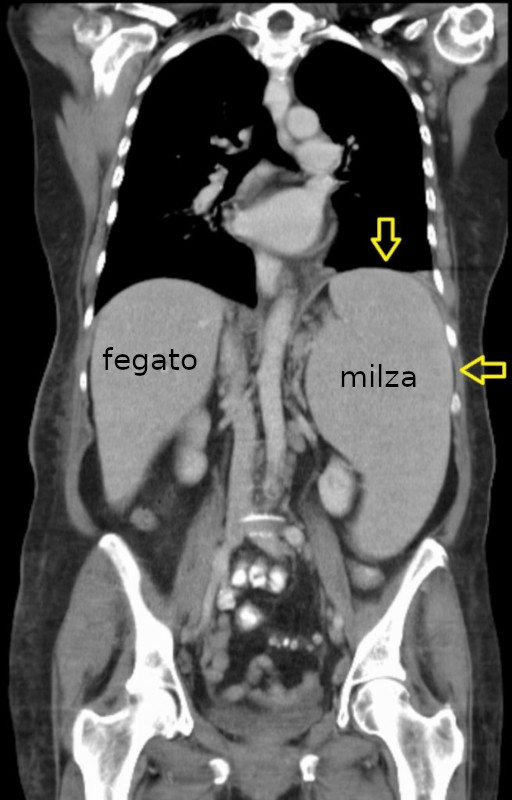

Splenomegalia

- Descrizione: La splenomegalia è un allargamento delle dimensioni della Milza.